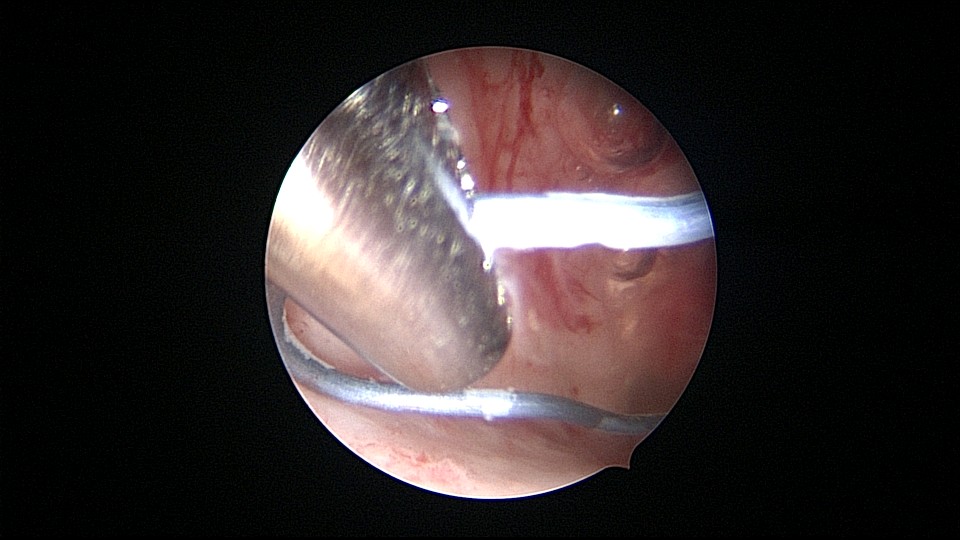

患者55岁,G4P1,顺产1次。安环16年,绝经5年,外院取环失败。子宫前位,宫颈萎缩,宫腔下段左后壁见假道,假道内见肌瘤结节突出,爱母环位置正常,宫腔左侧壁及前壁见占位质脆组织,表面有异常粗大血管。异物钳顺利取出节育环,占位组织病检为内膜样癌。取环造成的假道让病人因祸得福,提前发现了子宫内膜样癌,得以及时手术治疗。